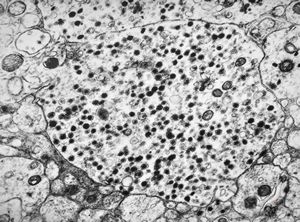

F, 71y. | carcinoid … metastasis to lymphonode